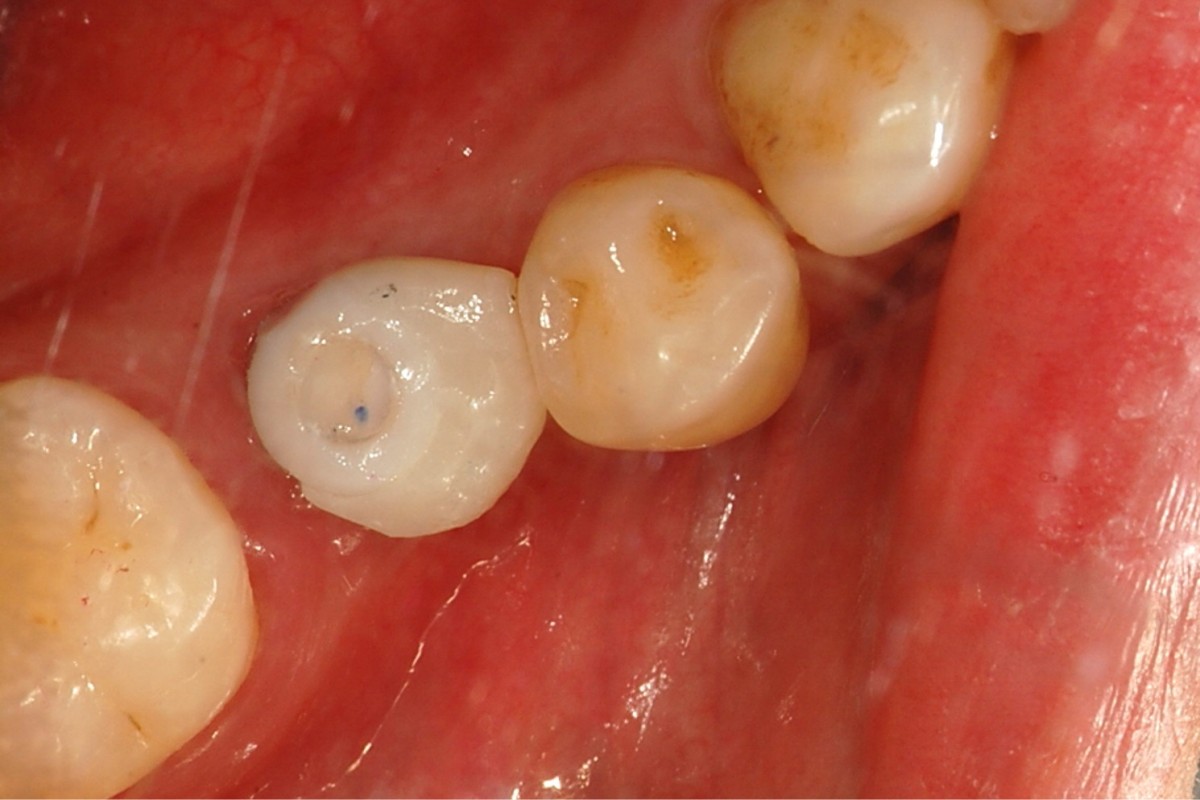

▲Remaining promary tooth